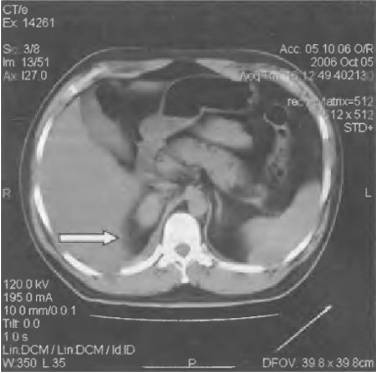

Гидронефроз

Прогрессирующее расширение собирательных полостей почек, которое приводит к их дисфункции.

Характер и локализация боли

Гидронефроз характеризуется ноющими болями в области живота, боков, поясницы и крестца.

При поражении правой почки болезненность ощущается преимущественно справа.

Дополнительные симптомы

К другим симптомам патологии относятся:

- прощупываемое уплотнение в брюшной полости;

- присутствие крови в моче;

- повышение температуры тела;

- озноб;

- головные и суставные боли.

При поражении обоих органов развивается почечная недостаточность, которая проявляется уменьшением количества выделяемой мочи, отечностью и повышением артериального давления.

Диагностика и лечение

Диагностировать заболевание можно при помощи анализа крови, УЗИ почек, экскреторной урографии, КТ и МРТ.